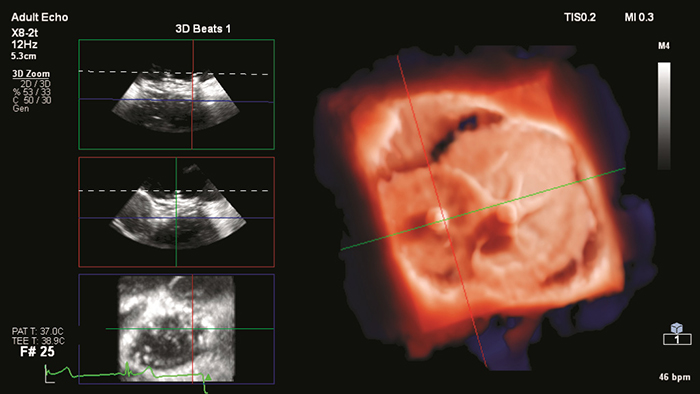

EchoNavigator reorients and combines ultrasound and X-ray information into a single augmented visualization for guidance and device-tissue relationship assessment. It enables: In the video above, courtesy of Dr. Jone, Colorado Chidren’s Hospital, the different features of EchoNavigator are illustrated during a mitral balloon valvuloplasty procedure.